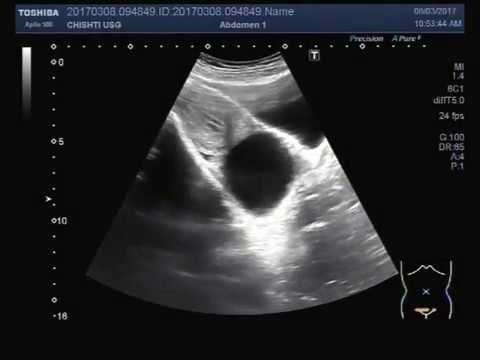

Vous réalisez une échographie pelvienne qui retrouve ceci :

Un myome est plus échogène, l’image ici est trans-sonore, totalement anéchogène = c’est du liquide pur

Voir commentaire général

Kyste fonctionnel = évolution kystique d’un follicule

Ce kyste va disparaître avec les cycles

On peut programmer un contrôle échographique dans trois mois dans le cadre d’une procréation médicalement assistée (PMA) car la présence du kyste peut fausser certains dosages utilisés dans le suivi d’une stimulation ovarienne

Pas de critères d’organicité, pas d’intérêt à réaliser une imagerie complémentaire par IRM

Pour exemple, voici un cliché de fibrome interstitiel, celui déforme la ligne endométriale et peut potentiellement gêner une implantation embryonnaire. Les critères d’organicité d’un kyste ovarien ont été définis par le groupe de travail IOTA (International Ovarian Tumor Analysis) en 2000.